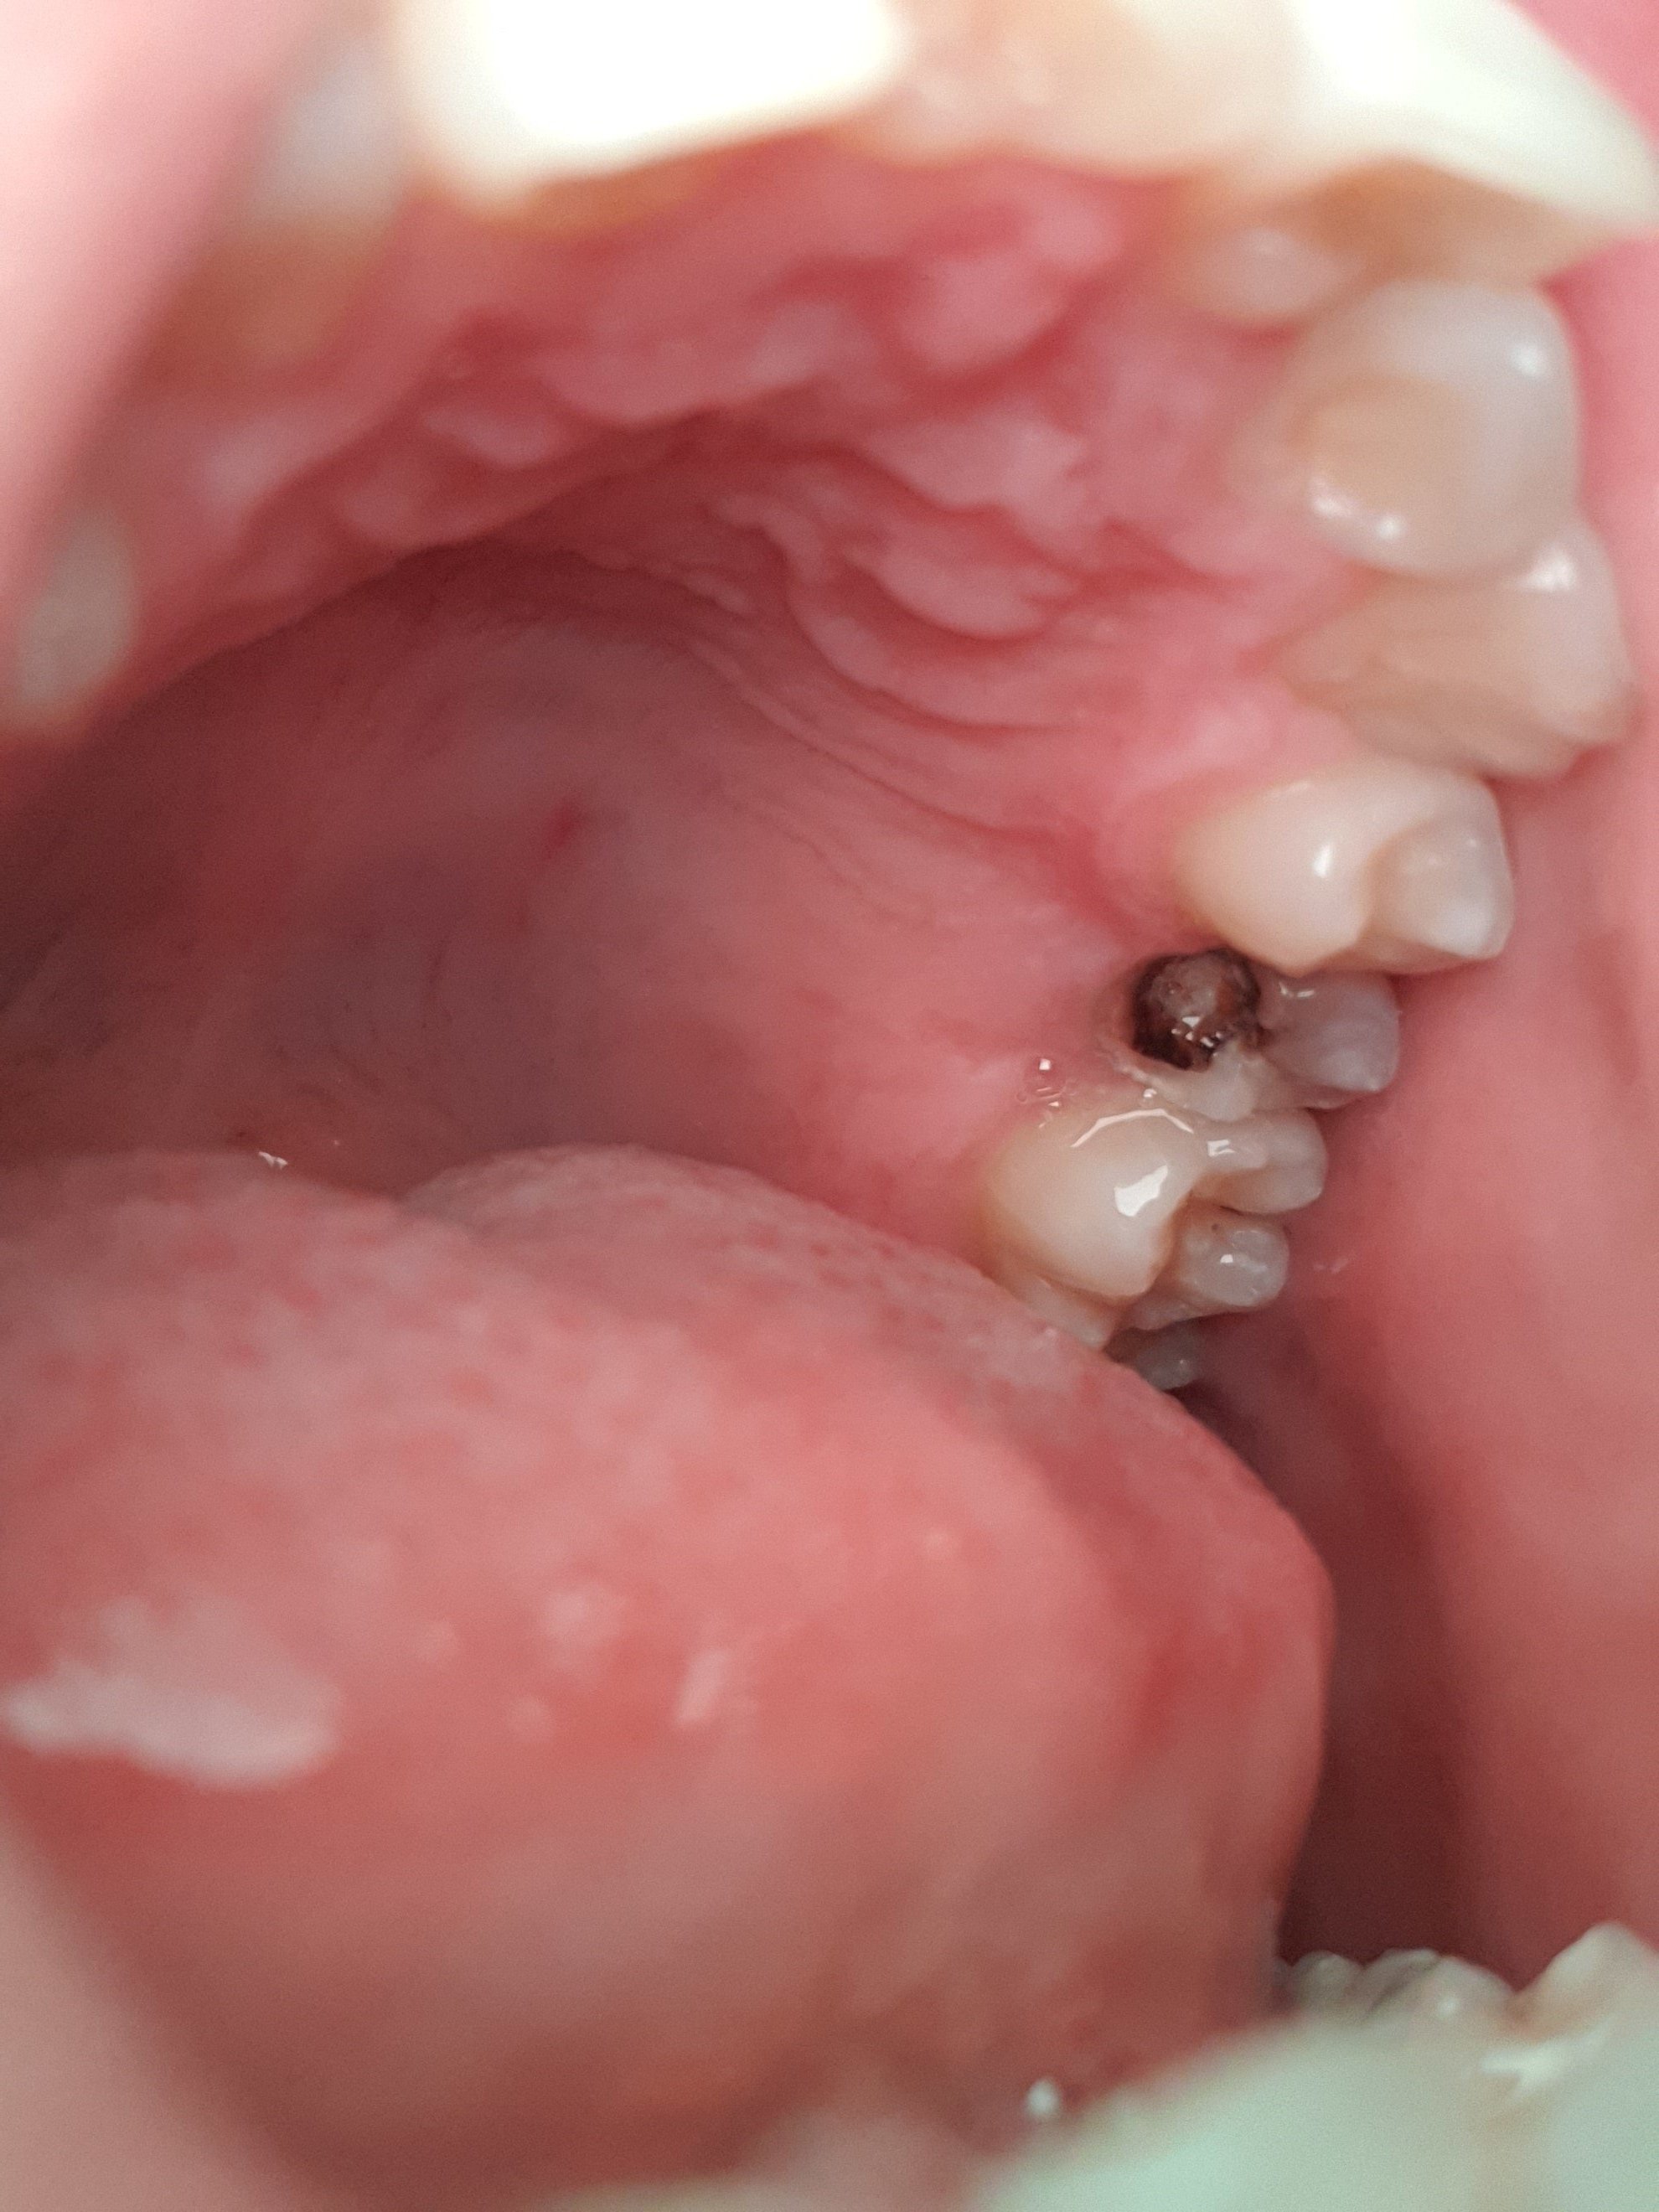

C'est une dent cassé à la base , je suppose que c'est plus susceptible de pourrir parceque je me lave les dents 2 fois par jours

La dent est morte tout simplement

Ça fait un moment qu'elle est dans cet état pourtant, au début c'étais une dent cassé à cause d'un coup

Ça fait peur à voir mais j'ai 0 douleur 0 sensationVa chez le dentiste quand-même ça me semble plutôt important, je prendrais pas le risque moi si j'avais cela.

Go soigner tes dents sans déconner gros, les problèmes dentaires ça se soigne bien, et en plus si tu attends trop tu risques des complications vraiment graves

Va chez le dentiste pour la faire retirer sinon tu prend le risque que ça s’étende vers les autres dent